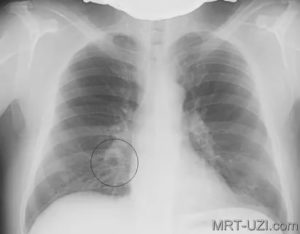

Рентген лёгких при пневмонии

Пневмония на рентгене дифференцируется по значительному числу параметров и признаков. Большое значение здесь имеет объём воспаления. Болезнь может затрагивать весь орган, половину или только малую часть.

Снимок при пневмонии расшифровывается по нескольким критериям: просветления, затемнения, изменение корней и рисунка органа. Обнаруживаемые пятна делятся на несколько групп:

• большие (тотальные, более 7 мм);

• средние (не более 7 мм);

• мелкие (около 3 мм).

Диагностируются единичные либо обширные поражения. Изменения указывают на такие формы болезни: очаговая, крупозная, казеозная.

Очаговая пневмония лучше всего видна на рентген снимке при разгаре патологии. Происходит снижение воздушности лёгочной ткани. По этой причине обнаруживаются тёмные пятна.

Сначала инфильтраты видны как «дымка». Затем формируется классический пневмонический очаг.

Крупозная пневмония на рентген снимке прослеживается в качестве большого среднеинтенсивного затемнения. Патологический процесс заметен на одной или обоих долях.

Обнаруживаются тотальные либо субтотальные тени. Купола диафрагмы поражаются. Прослеживается тяжистость корней.

Казеозная форма патологии является наиболее сложной. При рентгене обнаруживаются грубые и распространённые изменения. Затемнения присутствуют на большей части доли органа.

По мере нарастающего развития болезни появляются участки просветления. По форме и размерам они различны.